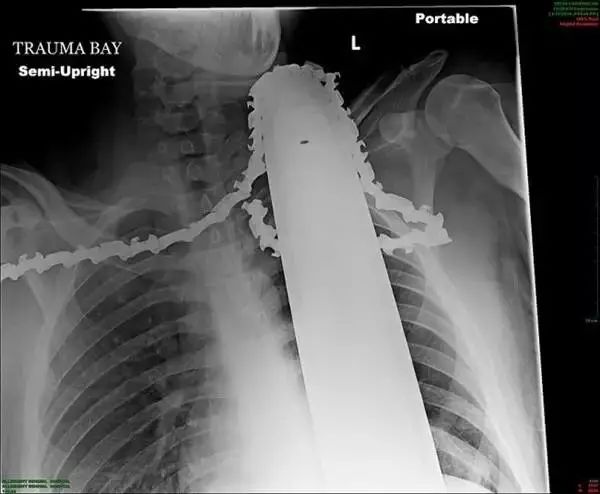

5、这张胸部透视片上可以看到这名患者的脖子到胸腔位置有一个电锯的锯链。当时患者正和同事们一同在伐木,突然电锯的链条断裂并反弹回来,切穿了患者的胸腔。